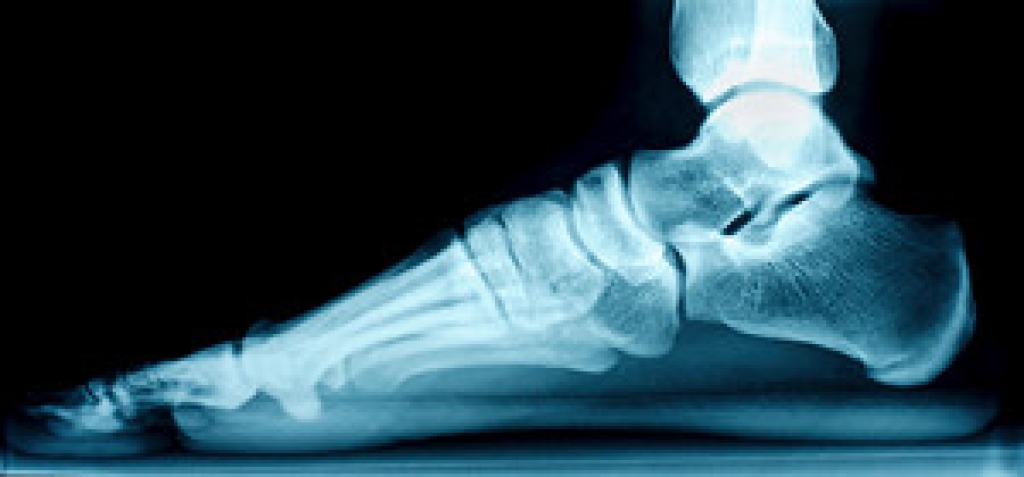

A hairline crack in a foot bone it's also known as a stress fracture. Frequently participating in running and jumping activities may cause stress fractures, which can happen from the repetitive force. A stress fracture can gradually occur, and many people choose to ignore the dull ache that accompanies this injury. When the pain becomes severe medical attention is often sought, and relief tactics are begun. Swelling may accompany a stress fracture, and walking can become difficult. A bone scan or an MRI can be performed to determine the extent of the fracture, as it may not be visible on an X-ray. Additionally, people who have osteoporosis or who consistently run on hard surfaces may be prone to getting a stress fracture. Treatment can begin by temporarily stopping the activity that caused the fracture, and elevating the affected foot may reduce the swelling. It may help to wear a protective boot that can provide the necessary stability as it heals. If you have a stress fracture of the foot, it is suggested that you confer with a podiatrist who can effectively diagnose and treat this condition.

Stress fractures are the result of repetitive force being placed on the bone. Since the lower leg and feet often carry most of the body’s weight, stress fractures are likely to occur in these areas. If you rush into a new exercise, you are more likely to develop a stress fracture since you are starting too much, too soon. Pain resulting from stress fractures may go unnoticed at first, however it may start to worsen over time.

Stress fractures do not always heal properly, so it is important that you seek help from a podiatrist if you suspect you may have one. Ignoring your stress fracture may cause it to worsen, and you may develop chronic pain as well as additional fractures.